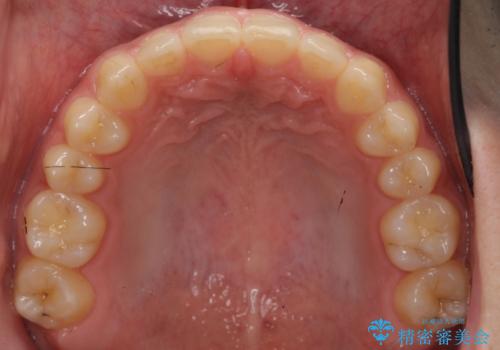

前歯のすきま 受け口 インビザラインで

治療症例の内容

- 治療計画

- 前歯のすき間を気にして来院。

受け口もあり、前歯が端同士であたる、切端咬合となっていました。

下の歯のすき間を閉じて上の歯の内側に入るように位置付けました。

すき間もきれいに閉じ、満足していただきました。

上の前歯は下の歯と直接へりが当たっていた状態(切端咬合)だったため、形がいびつだったのは、わずかにやすりがけをして整えました。

セラミックですき間を閉じようとすると、すきまをうめるために巨大な歯になり、また、下の歯が前に出て強く当たるため、セラミックがかけるおそれがあります。また、下の歯をさけようとすると角度をかえるために歯を極端に削らなければならなくなり、神経をとらなければいけなくなるリスクもあります。

このような歯並びは、セラミックでかぶせるよりは、矯正治療の

適応と言えます。